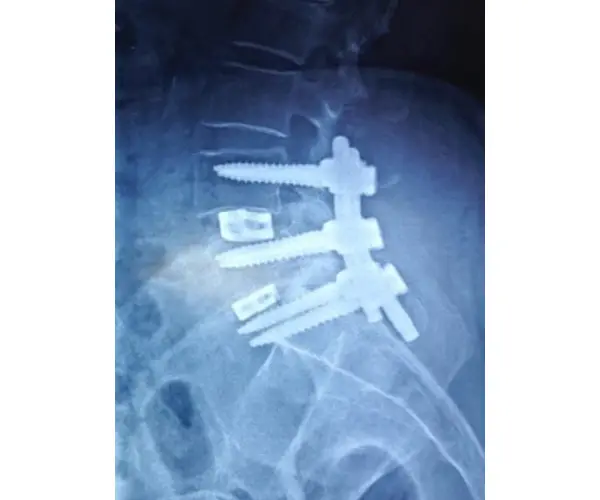

Open Lumbar Fusion

Minimally Invasive Lumbar Fusion